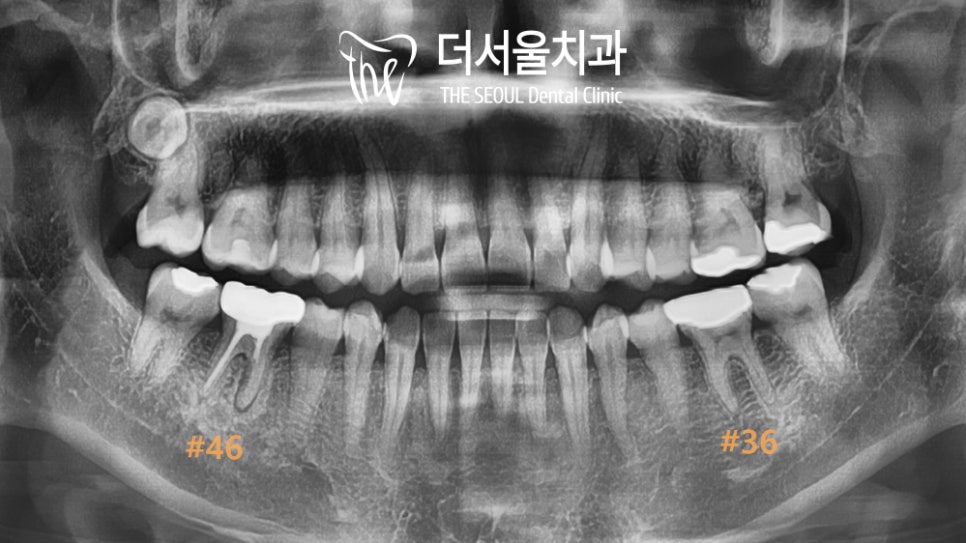

【 양쪽 어금니가 아파요. 】

아래 양쪽 어금니가 아프다며

찾아오셨던 분입니다.

왼쪽은 씹을 때마다 아프다고 하셨고

오른쪽은 가만히 있을 때도

욱신거리고 찌릿하다는 말을 하셨는데요.

치근단 방사선으로 확인해 본

오른쪽은 뿌리가 갈라지는

분지부부터 앞쪽 뿌리 주변이

검게 변해 있는 것을 볼 수 있습니다.

또한 이전에 진료를 받았다는 것을

채워진 근관 내 충전재를 통해 알 수 있었죠.

왼쪽은 이차우식으로 인해 염증이 생겨

불편함이 생긴 것으로 확인되었습니다.